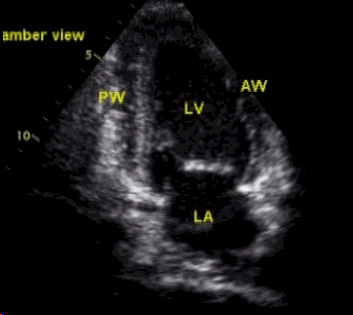

使用双切面(二腔室+四腔室)超声心动图数据训练Mamba模型诊断早期心梗的需求,设计了一个创新性的双路径时空融合Mamba架构(Dual-Path Spatiotemporal Fusion Mamba, DPSF-Mamba)。该架构针对性解决多切面心脏超声的时空特征融合问题,核心思路如下:

独立编码路径:为二腔室(2C)和四腔室(4C)切面分别设计专用Mamba块,适应不同视角的局部结构特征。

2C路径:聚焦左心室前壁、心尖部运动异常(早期心梗敏感区域)。

4C路径:捕获室间隔、侧壁运动及整体心室协调性(诊断关键指标)。